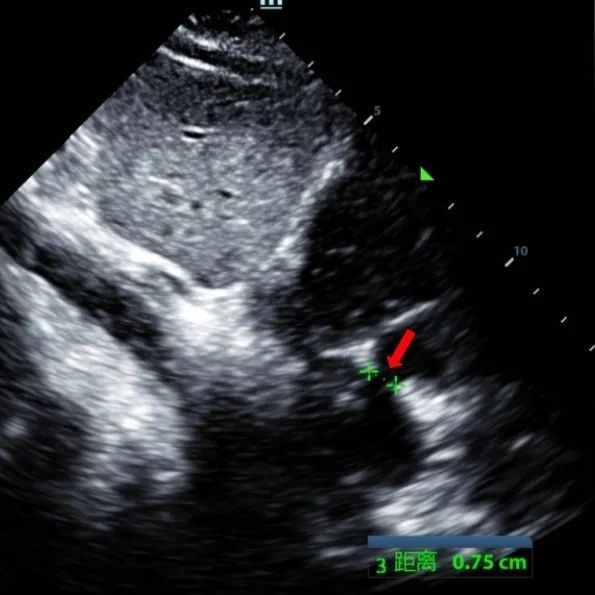

Laki-laki 9 tahun dengan secundum ASD (7.5-7.9mm) diperlakukan menggunakan MemoSorb BDASD-I 12mm occluber dan sistem pengiriman 12F. Tidak ada penyakit komplikasi atau komposit, pra-prosedur.

Serial echocardiographic follow-ups showed stable device position and favorable cardiac remodeling. Gradual degradation confirmed the occluder's long-term safety and efficacy.